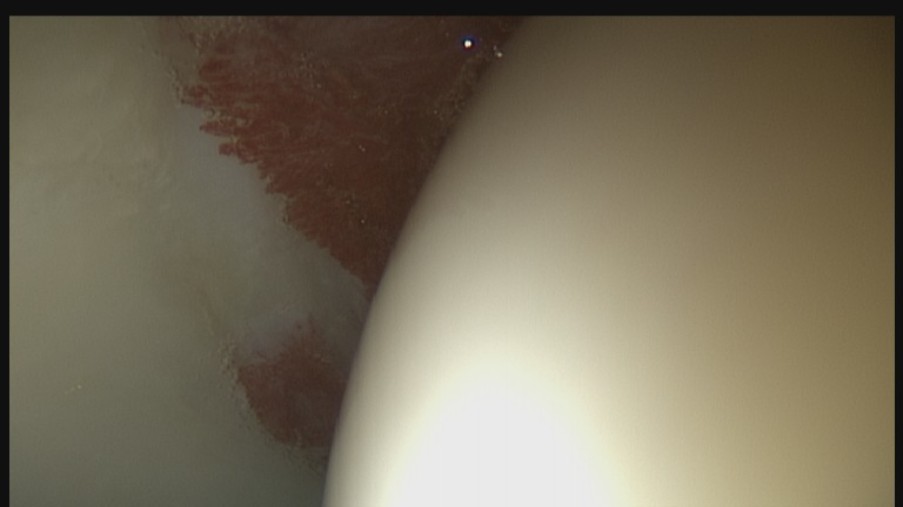

Bei der Arthroskopie handelt es sich um ein minimalinvasives Verfahren, das einen sehr guten Heilungsverlauf besitzt. Bei Erkrankungen und Veränderungen im Hüftgelenk und am Hüftkopf bzw. Schenkelhals kann eine Hüft-Arthroskopie durchgeführt werden.

Im Gegensatz zu der Spiegelung des Kniegelenks ist die Spiegelung des Hüftgelenks ein anspruchsvolleres Verfahren. Dies hängt damit zusammen, dass das Hüftgelenk sich sehr nah an den Gefäßen und Nerven des Beins befindet. Das Operationsteam der LVR-Klinik für Orthopädie Viersen bringt daher eine exakte Kenntnis der Anatomie mit und ist gut geschult.